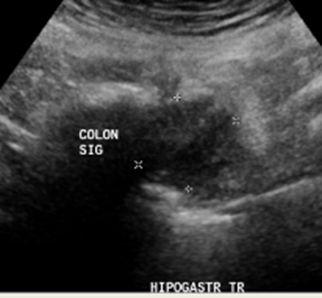

A nivel de hipogastrio se observa un engrosamiento focal de colon (colon sigmoide) con aumento de ecogenicidad de grasa adyacente, leve señal al doppler, doloroso al paso del transductor, podría corresponder a diverticulitis ¿? Tumoral ¿? Se sugiere complementar con TAC

A nivel de hipogastrio se observa un engrosamiento focal del colon sigmoides con aumento de la ecogenicidad de la grasa adyacente y leve señal y doloroso al paso del transductor

Impresión diagnóstica: Los hallazgos descritos a nivel de hipogastrio podrían estar en el contexto de un proceso inflamatorio intestinal inespecífico diverticulitis ¿? Tumoral ¿?